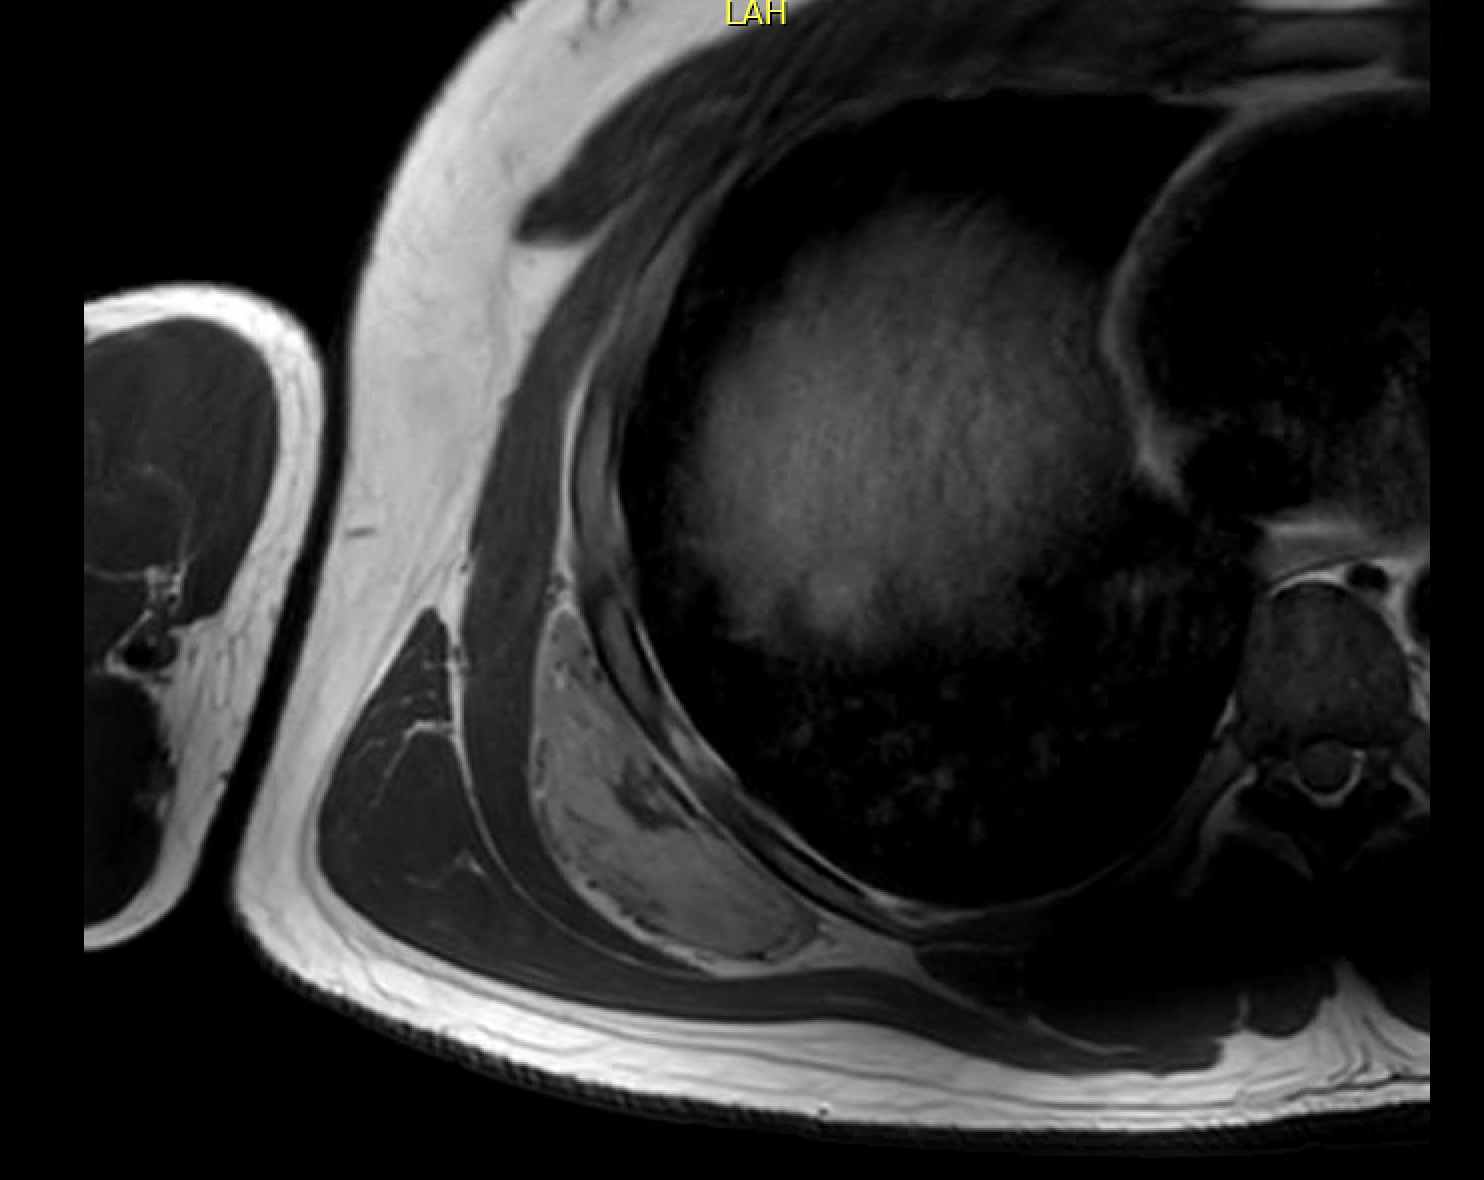

MRI

Semilunar, soft tissue mass abutting the rib cage posteriorly with well defined margins

Similar signal intensity to muscle